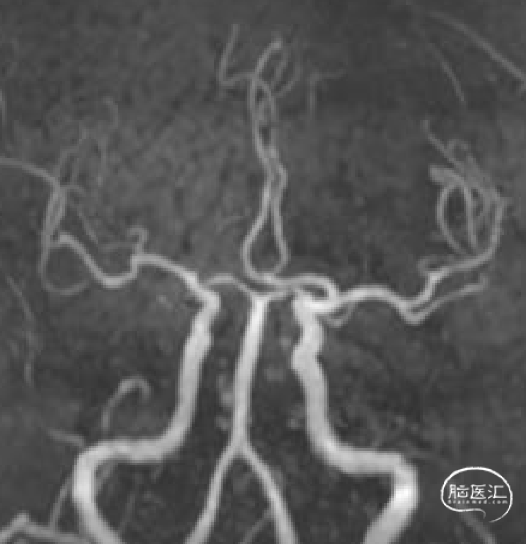

出院复查MRA及血栓病理如下:

出院复查MRA